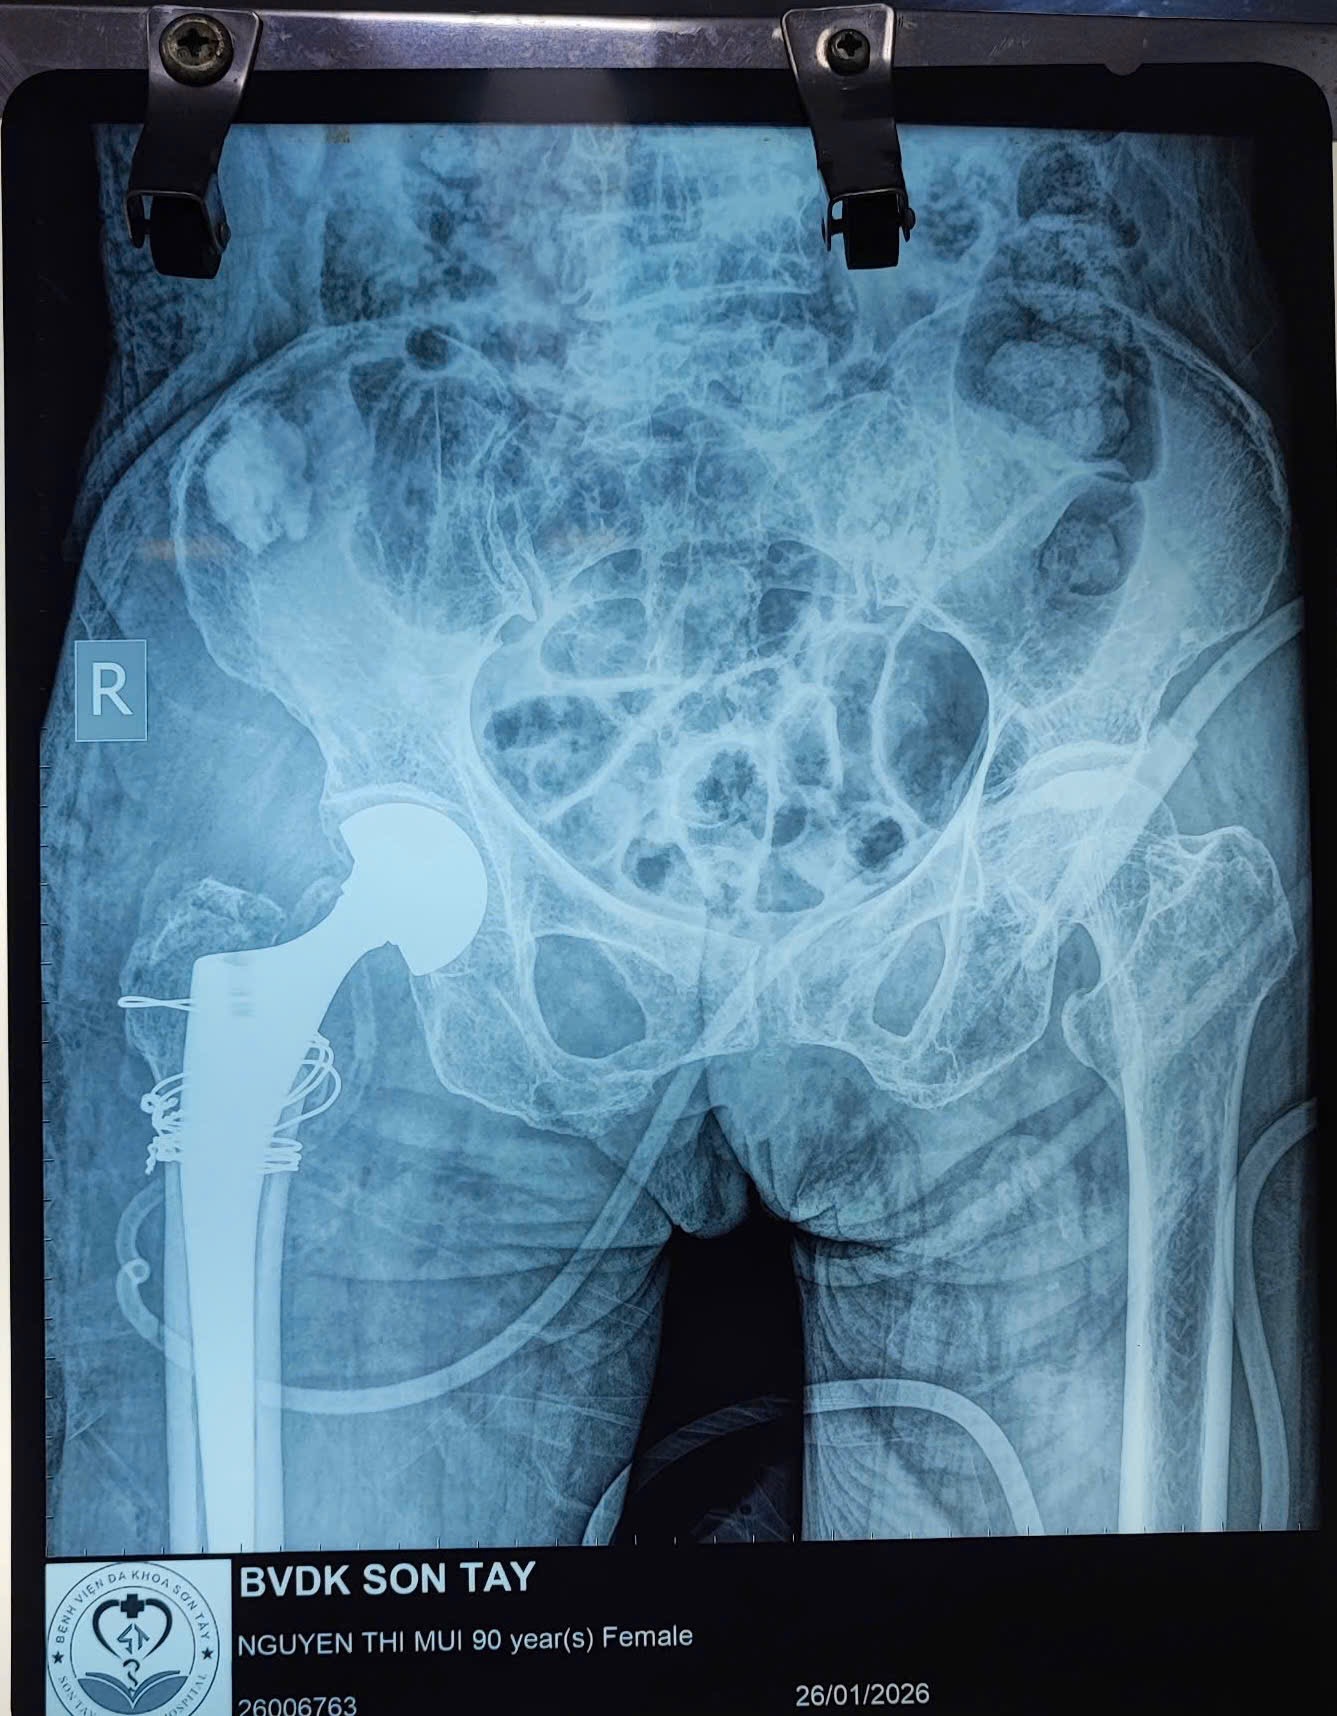

📅 Ngày 26/01/2026, Khoa Ngoại Chấn thương – Bệnh viện Đa khoa Sơn Tây đã phẫu thuật thành công thay khớp háng bán phần cho bệnh nhân Nguyễn Thị M. (90 tuổi ở Yên Thành, Suối Hai, Hà Nội)

🩺 Bệnh nhân nhập viện trong tình trạng gãy phức tạp vùng liên mấu chuyển/cổ xương đùi phải trên nền loãng xương nặng, kèm nhiều bệnh lý nội khoa như tăng huyết áp, suy tim. Theo người nhà, bệnh nhân bị ngã tại nhà, đau nhiều vùng háng – đùi phải, không thể đi lại.

📸 Kết quả X-quang và CT cho thấy tổn thương phức tạp đầu trên xương đùi, nguy cơ cao nếu điều trị bằng phương pháp kết hợp xương thông thường. Sau hội chẩn liên chuyên khoa (Ngoại Chấn thương, Gây mê hồi sức, Nội tim mạch), ê-kíp điều trị thống nhất chỉ định thay khớp háng bán phần nhằm giúp bệnh nhân giảm đau nhanh, vận động sớm, hạn chế biến chứng do nằm lâu.

👨⚕️ Ca phẫu thuật được thực hiện an toàn, ít xâm lấn, thời gian mổ ngắn, kiểm soát huyết động tốt. Sau mổ, bệnh nhân tỉnh táo, các chỉ số sinh tồn ổn định, được hướng dẫn tập vận động sớm, góp phần giảm nguy cơ viêm phổi, loét tỳ đè và thuyên tắc mạch.